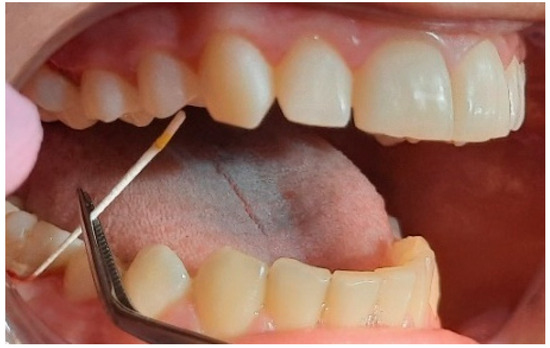

2.2. Clinical Examinations

2.3. Sampling for PCR

2.5. Specialist Treatment